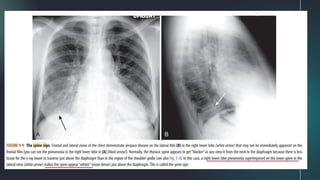

ROUND PNEUMONIA

SILHOUETTE SIGN

● On the lateral chest radiograph, the thoracic spine

normally appears to get darker from the shoulder girdle to

the diaphragm.

● When diseases of soft tissue or fluid density involves the

posterior portion of the lower lobe, more of the x-ray beam

will be absorbed by the new, added density, and the spine

will appear to become “whiter” just above the posterior

costophrenic sulcus.

SPINE SIGN